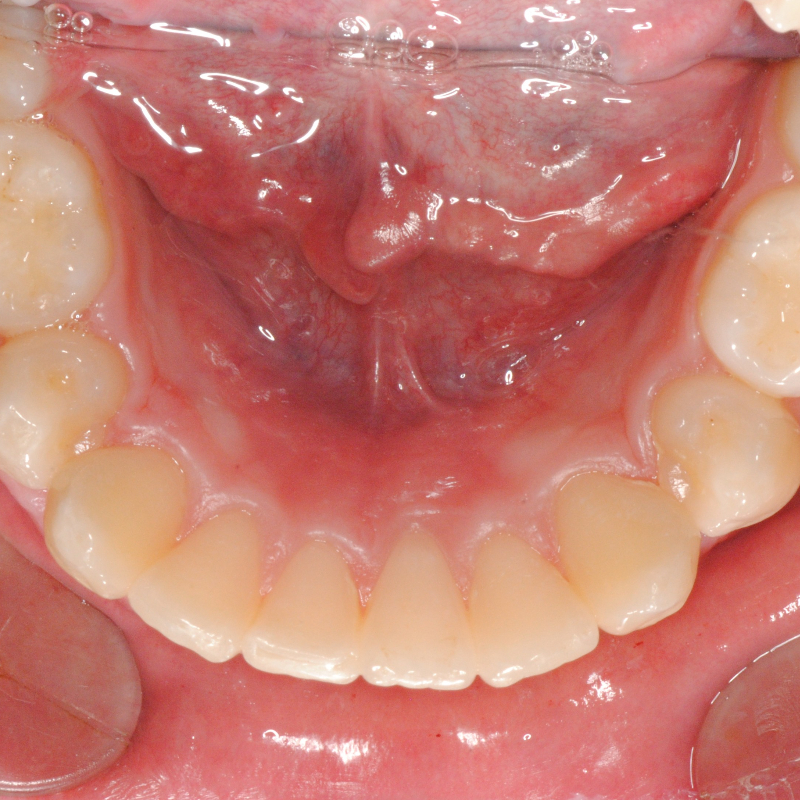

Prima e dopo trattamento con ortodonzia invisibile per l’allineamento dei denti